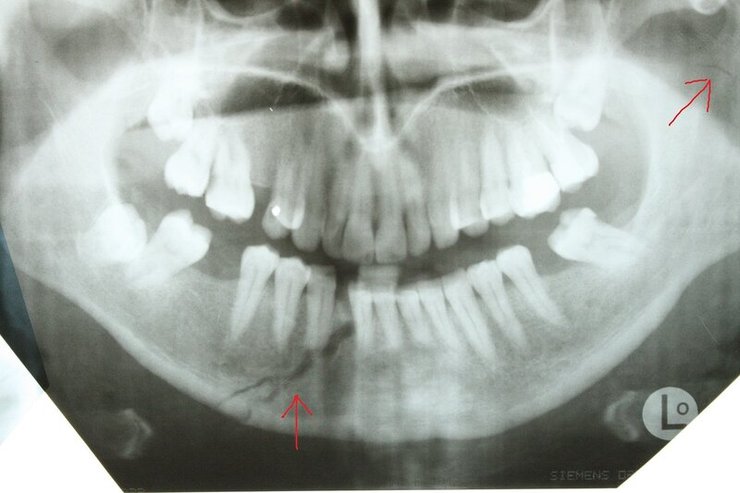

Челюсть Адама Кадырова NIYSO

Сын главы Чечни Рамзана Кадырова Адам Кадыров мог сломать челюсть, когда попал в ДТП. Кроме этого, он имеет еще ряд менее значительных травм.

Авторы отмечают, что характерный для такой травмы отек лица спадает лишь через 1-2 недели. А на то, чтобы снять фиксацию челюсти, понадобится примерно месяц.

Также в результате аварии у Кадырова-младшего могли появиться рваные раны, рассечения, разрывы кожи и гематомы. Из-за этого может понадобиться еще несколько недель, чтобы скрыть последствия аварии.